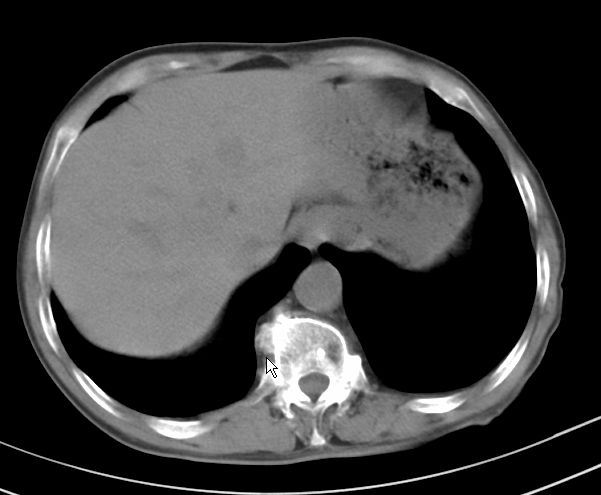

楼主说是炎症,凭啥?典型的周围型肺癌(腺癌可能性大),肝内可能已有转移,强化看看吧。